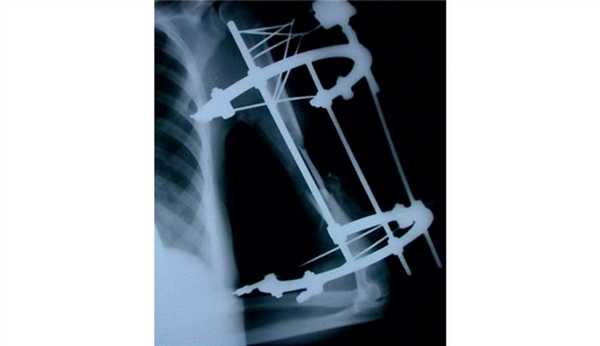

Пример дефицита кости гленоида и головки плечевой кости при множественных вывихах плечевого сустава